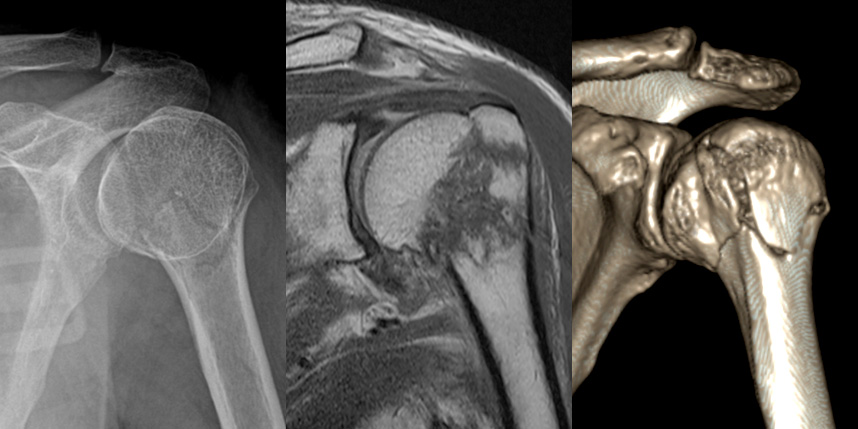

상완골 골절